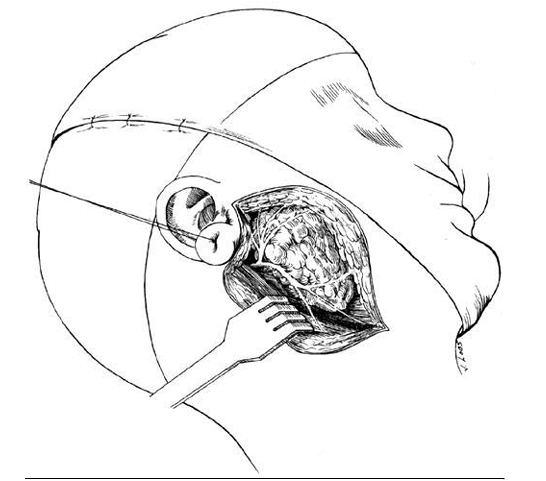

ورم مختلط في الغدة النكفية (من أرشيف الدكتور فهد شريباتي )

تقسم أورام الغدد اللعابية السليمة والخبيثة منها إلى أورام ظهارية ، و غير ظهارية وانتقالية . تشمل الأورام الظهارية السليمة الورم الغدي عديد الأشكال pleomorphic adenoma 80%، الورم الغدي وحيد الشكل monomorphic adenoma ، ورم وارثون Warthin's tumor ، ورم الخلايا الحمضية oncocytoma ، والتنشؤات الزهمية sebaceous . أما الآفات السليمة غير الظهارية فتشمل كلاً من الورم الوعائي ، و أورام الغمد العصبي، والورم الشحمي . تعالج جميع الأورام السليمة بالاستئصال الجراحي للغدة المصابة أو استئصال الفص السطحي فقط في حال إصابة النكفة مع تسليخ العصب الوجهي والحفاظ عليه.

بشكل عام تبقى الجراحة المعالجة الأساسية لخباثات الغدد اللعابية عموماً وتشمل المبادئ الجراحية الأساسية استئصال الغدة المصابة ككتلة واحدة مع الحفاظ على جميع الأعصاب إلا إذا كانت مرتشحة بالورم وفي حال إصابة الفص الوحشي من النكفة فقط فيستطب استئصال الفص السطحي للغدة النكفية والمحافظة على العصب الوجهي وتفرعاته وكذلك الأمر حتى في حال امتداد الورم للفص العميق للنكفة يجب دوما بذل الجهد للحفاظ على العصب الوجهي إلا إذا كان مصابا ومرتشحاً بالغزو الورمي المباشر . وتطبق المعالجة الشعاعية الرادفة بعد الجراحة في حالات خاصة